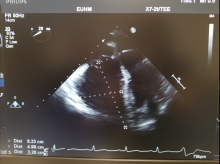

Surgical pulmonary embolectomy (SPE) is a safe and effective therapeutic approach to pulmonary embolism management for patients who are diagnosed with submassive and/or massive acute pulmonary emboli by clinical exam, supported by computed tomography (CT) and echocardiographic assessment. Other indications for surgical embolectomy include presence of thrombus-in-transit, concomitant cardiac pathology such as a large patent foramen ovale, or relative contraindications to thrombolytic therapy, including recent cerebrovascular or intracranial pathology, recent surgery, active bleeding, or other absolute contraindications to anticoagulation.

- Use the Seldinger technique to access the common femoral vein as follows: Access the vein with a needle and subsequent wire. Serially dilate the vessel to the size of the cannula. Insert venous cannula (25 French venous cannula) and position within the right atrium under TEE guidance. Connect venous line to bypass circuit.